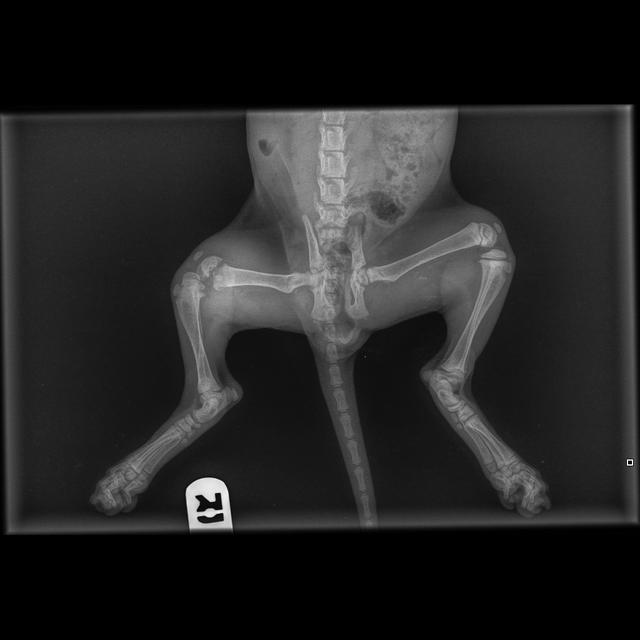

Merlin is a stray kitten rescued on Christmas Eve from Ranfurly St, Upper Hutt. Unfortunately Merlin came into care with a limping back leg. X-rays show an extremely rare break - a fracture of the growth plate in his femur.

Our vets are going to seek an orthopaedic opinion, but for now they have done their best to immobilize the leg with a splint which certainly isn't slowing him down one bit!

We do think amputation may be for the best, but would like to go ahead with an orthopedic opinion first. He's such a sweet spirited kitten and isn't too bothered by the cast. Unfortunately we simply don't have the costs to cover orthopaedic surgery (likely to be well over 5K) and long term costs - but regardless, the most important thing is the long term health and well-being of the kitten, and what's best for them.